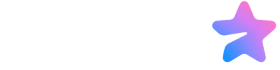

نوک سینه و آرئول (هاله اطراف نوک سینه) بخشهای حساسی از سینه هستند که در دوران بارداری، شیردهی و تغییرات هورمونی دستخوش تغییرات میشوند. لکههای سفید معمولاً به صورت نقاط کوچک سفید، زرد یا شفاف ظاهر میشوند و میتوانند دردناک یا بدون درد باشند. طبق منابع پزشکی، این لکهها اغلب نتیجه انسداد منافذ نوک سینه یا واکنش طبیعی بدن به هورمونها هستند. همچنین، تحقیقات اخیر نشان میدهد که عفونتهای قارچی (مانند برفک) کمتر از آنچه قبلاً تصور میشد، شایع هستند و اغلب علائم مشابه به دلیل درماتیت یا انسداد مجاری ایجاد میشوند.

1. تغییرات هورمونی و بارداری (غدد مونتگومری)

یکی از اولین نشانههای بارداری، بزرگ شدن غدد مونتگومری است. این غدد کوچک اطراف نوک سینه و آرئول قرار دارند و مادهای روغنی ترشح میکنند که نوک سینه را مرطوب نگه میدارد و به نوزاد کمک میکند تا نوک سینه را پیدا کند. در دوران بارداری، این غدد ممکن است به صورت لکههای سفید یا برآمدگیهای کوچک ظاهر شوند. این وضعیت کاملاً طبیعی است و پس از زایمان یا بازگشت هورمونها به حالت عادی، برطرف میشود. همچنین، تغییرات هورمونی ناشی از قاعدگی، مصرف قرصهای ضدبارداری یا یائسگی میتواند باعث ظاهر شدن این لکهها شود.

2. انسداد منافذ یا مجاری شیری (بلب شیر یا تاول شیری)

این یکی از شایعترین علل در دوران شیردهی است. هنگامی که شیر خشکشده منافذ نوک سینه را مسدود میکند، لکه سفید (بلب شیر) تشکیل میشود. اگر پوست روی آن رشد کند، به تاول شیری تبدیل میشود. این وضعیت میتواند دردناک باشد و با قرمزی و التهاب همراه باشد. عواملی مانند تخلیه ناکافی شیر، شیردهی نامنظم یا لچ ضعیف نوزاد این مشکل را تشدید میکنند. زنان با تولید شیر زیاد بیشتر در معرض خطر هستند.